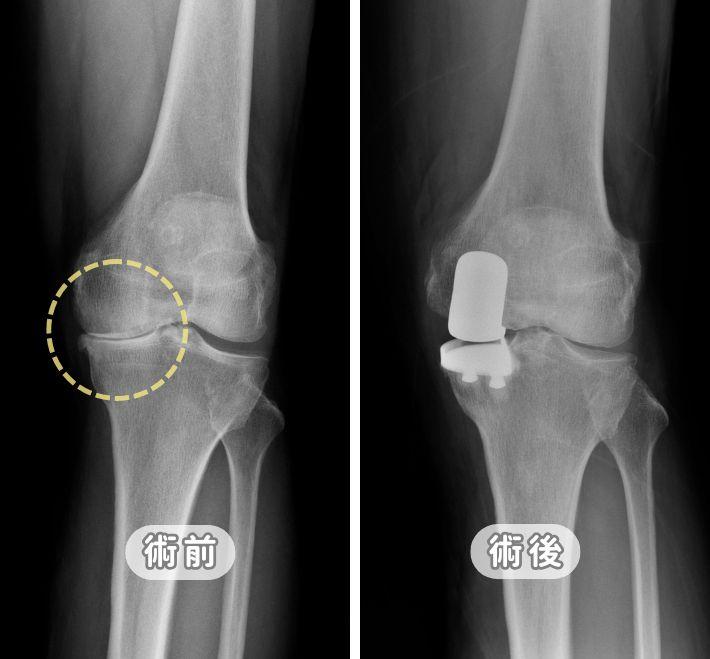

【告別膝關節退化】治療全攻略:初期症狀、復健運動到人工關節置換,醫師詳解保膝關鍵

膝蓋痛一定要換關節嗎?張建鈞主任詳解膝關節退化 K-L 四階段診斷。從初期的減重、股四頭肌訓練,到 PRP 與羊膜生長因子注射,本文提供完整階梯式療法。針對重度退化,深入對比「半膝」與「全膝」置換優劣,並解析 ROSA Knee 機器人手臂如何達成 0.1 公分精準骨切除,助您術後 24 小時下床,重拾行動尊嚴。